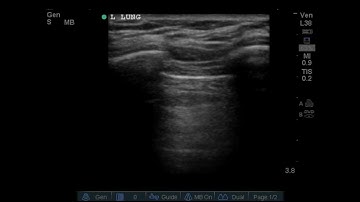

Lung Sliding with Linear Transducer